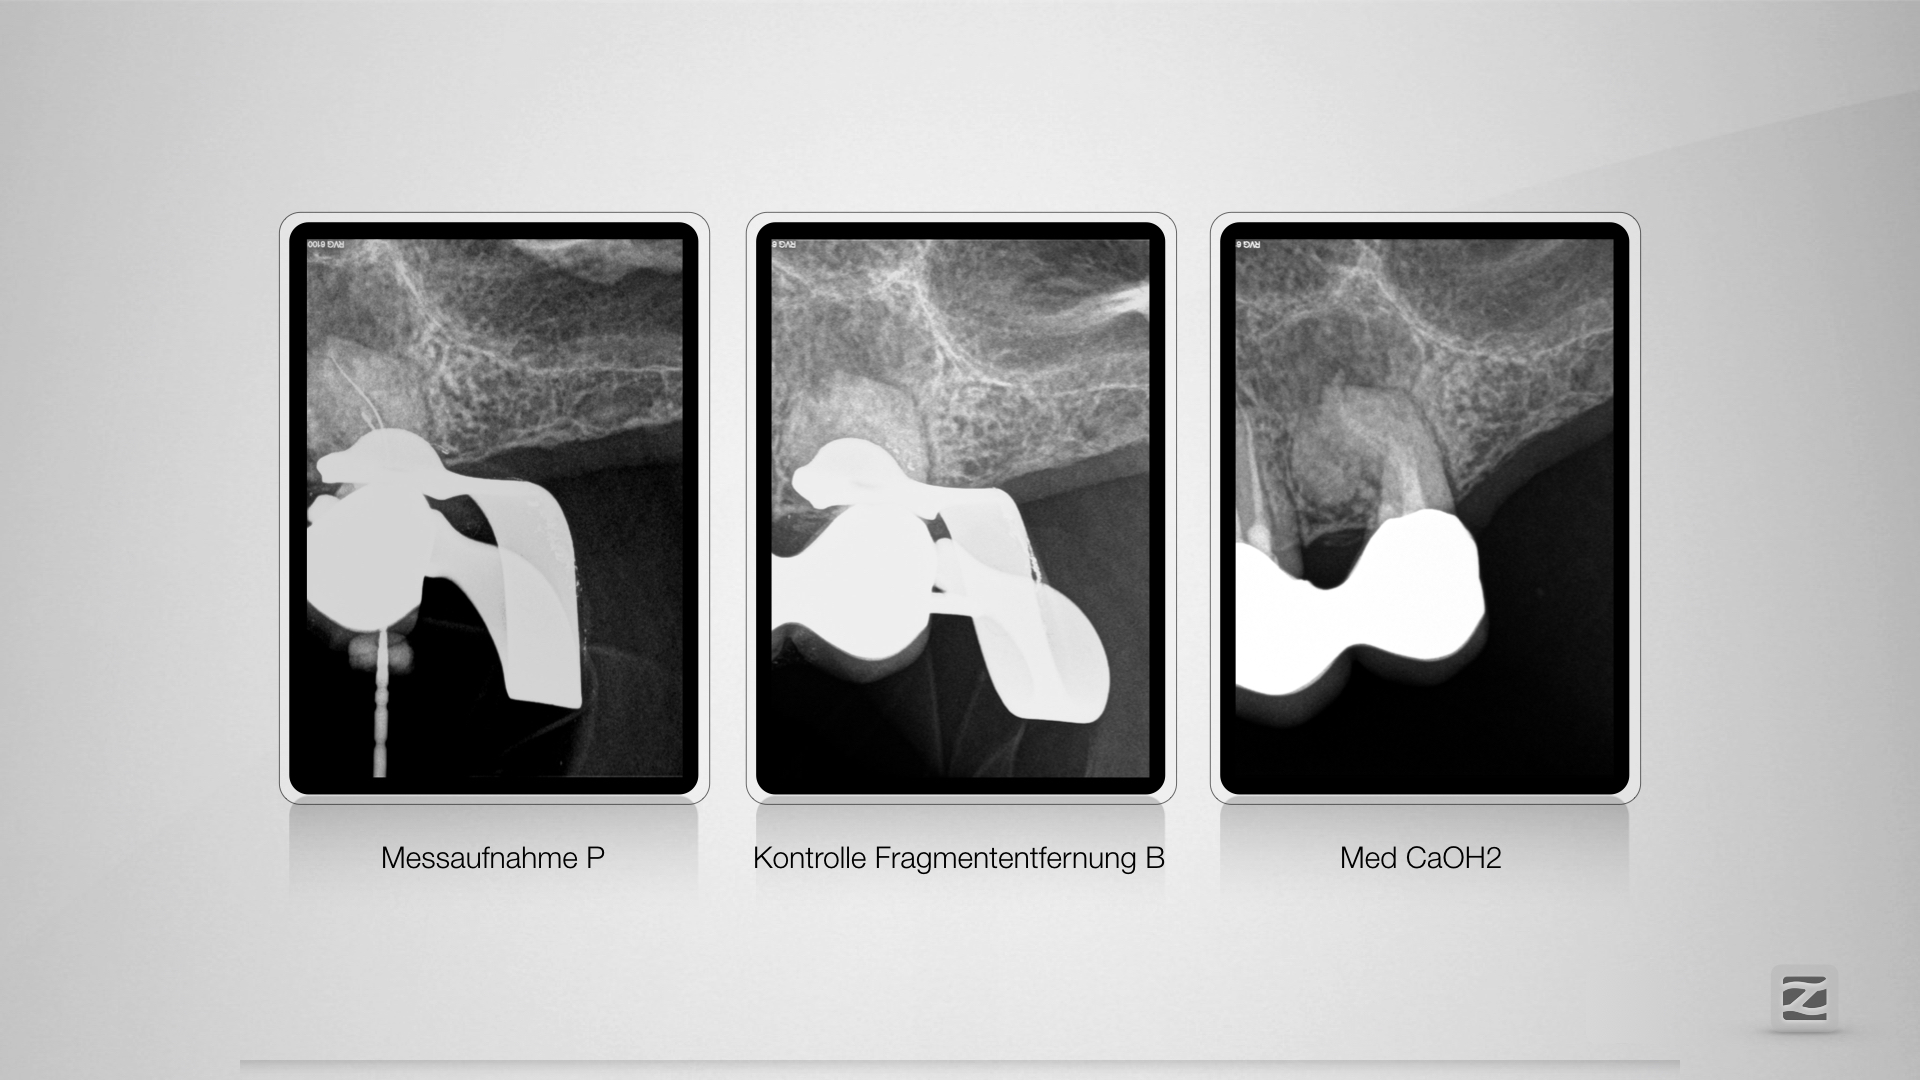

Mit Überlegung (2)